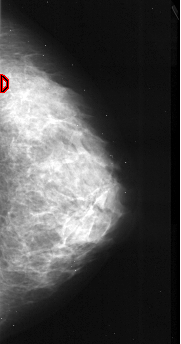

A_1041_1.RIGHT_CC

RIGHT_CC LINES 4126 PIXELS_PER_LINE 2161 BITS_PER_PIXEL 16 RESOLUTION 42 OVERLAY

FILE: A_1041_1.RIGHT_CC.OVERLAY

TOTAL_ABNORMALITIES 1

ABNORMALITY 1

LESION_TYPE CALCIFICATION TYPE PLEOMORPHIC DISTRIBUTION CLUSTERED

ASSESSMENT 4

SUBTLETY 2

PATHOLOGY MALIGNANT

TOTAL_OUTLINES 1

BOUNDARY